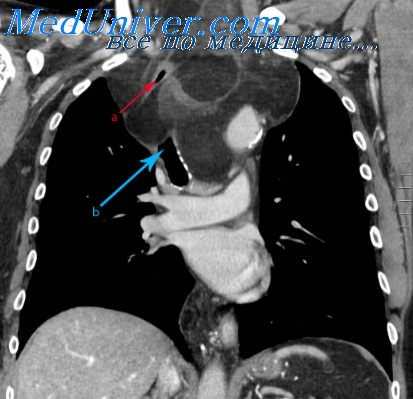

Воздушная эмболия — наиболее грозное, быстро развивающееся и нередко смертельное осложнение при операциях на средостении. Обычно она возникает при повреждении крупных, неспадающихся вен груди, а также полостей сердца. При воздушной эмболии воздух из вскрытой и неспадающейся вены в силу присасывающего действия венозной системы и сердца поступает в первую половину сердца, а затем в легочную артерию, закупоривая ее крупные и более мелкие ветви (венозная эмболия). Этот вид эмболии встречается чаще всего, так как артериальная воздушная эмболия наступает при ранении левой половины сердца или при незаращении перегородок сердца.